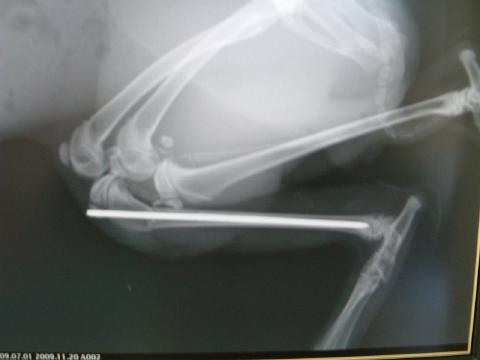

レントゲン検査:

下腿骨の骨幹やや近位で横骨折があり、大きく変位あり。

ピンニングにより整復された術後のレントゲン写真です。

骨折端の多少のずれはありますが、問題はありません。